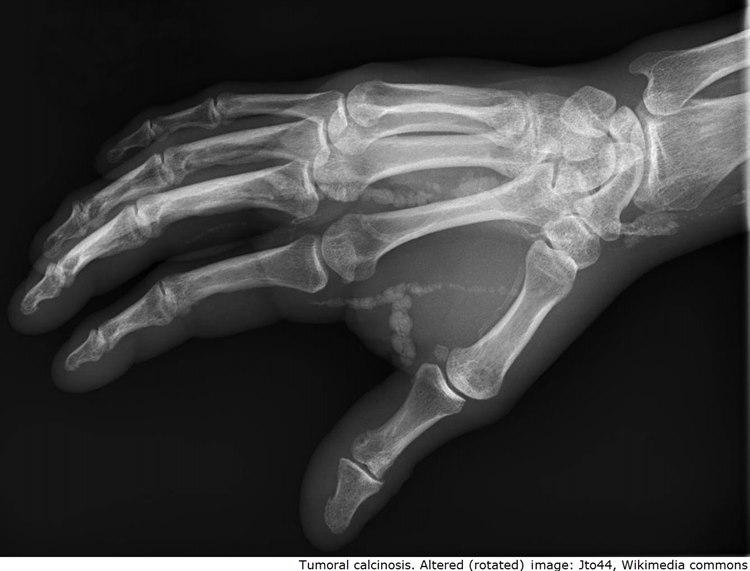

Tumoral kalsinose

Palpable avleiringer rundt ledd, særlig ved hofter og skuldre. Kan lett mistenkes for å være kreft

Typisk klinikk og histologi. Radiologiske funn. Hyperfosfatemi. Ev. lett forhøyet paratyroid funksjon, serum kalsium, urinsyre og ALP